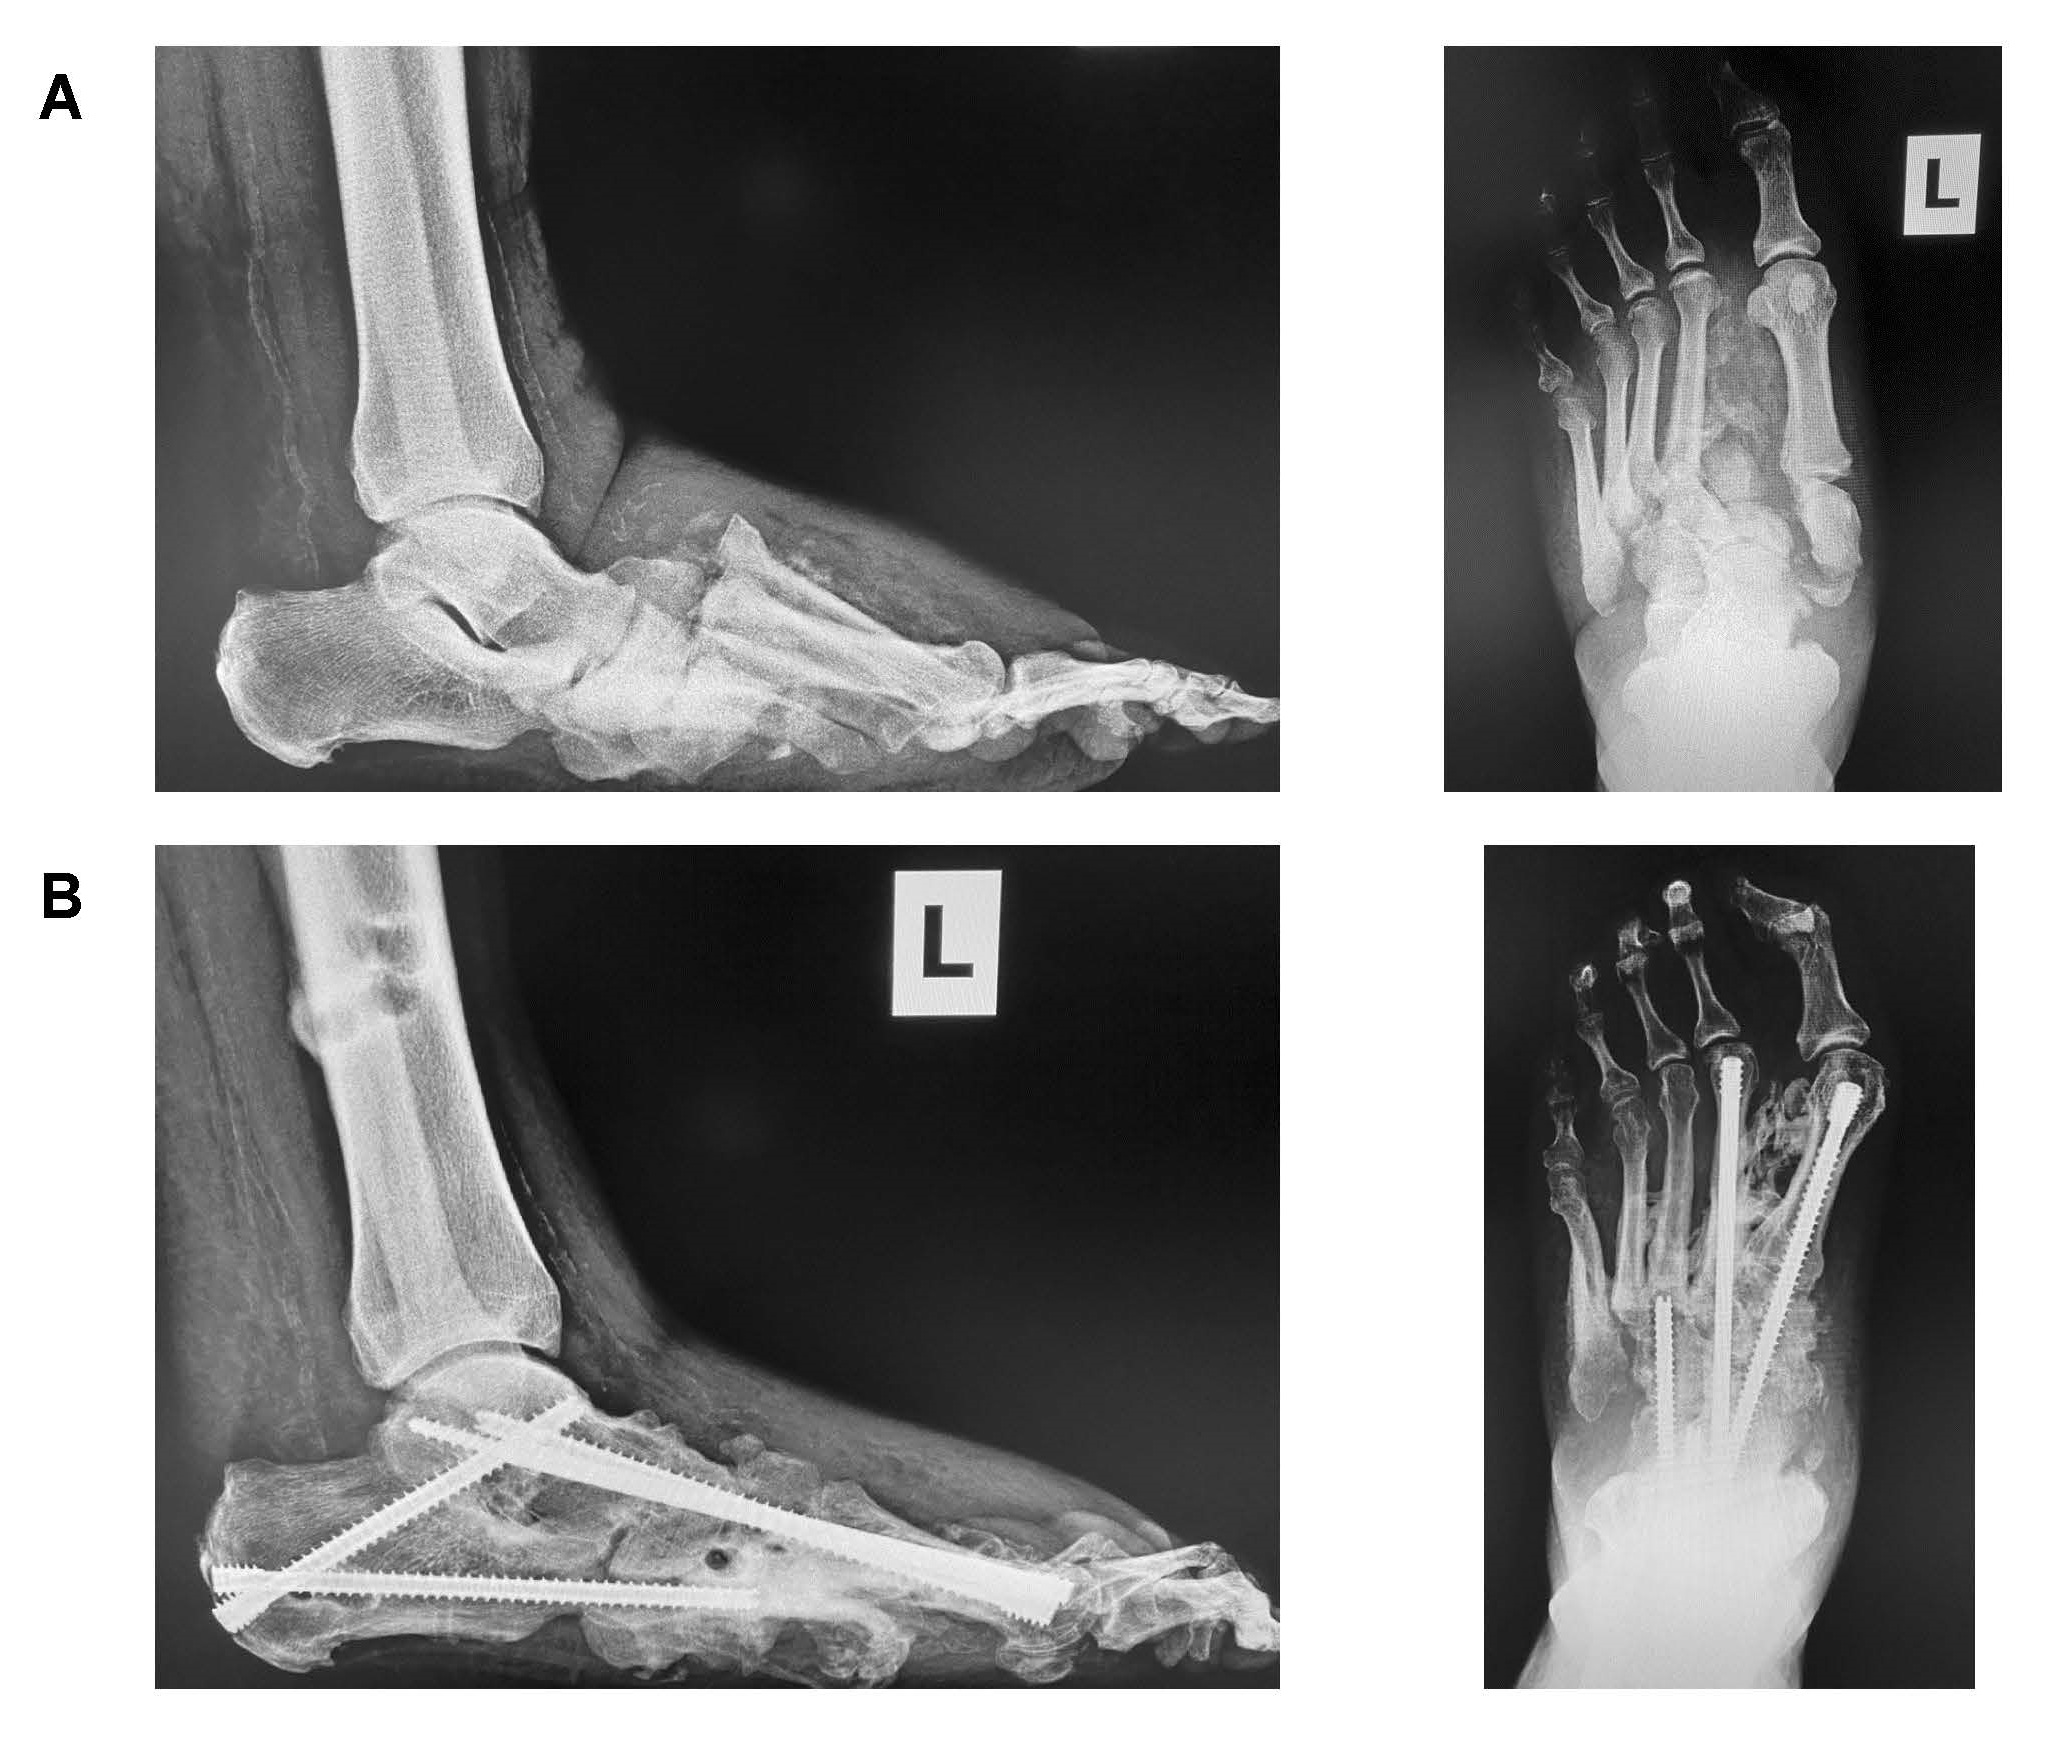

Patients who participated in the study presented with unstable foot and/or ankle deformities developed from CN. After standard foot and ankle radiographs were obtained along with advanced imaging studies (Magnetic Resonance imaging and/or Computed Tomography (CT) scans), if needed, along with a clinical evaluation, patients discussed their treatment options before electing to undergo a surgical reconstruction to realign and stabilize the deformity. The standard surgical procedure had the patient placed in a supine position on the operating table under general or spinal anesthesia along with the use of a thigh tourniquet. Patients had standard joint prep at the affected joints with curettage, rotatory burring along osteotomies as needed to realign the deformity. Patients who had tarsometatarsal and navicular-cuneiform joint deformities with no ankle instability or severe equinus deformity underwent a midfoot reconstruction that included midfoot osteotomy with realignment, medial and lateral column fusion, and subtalar joint fusion with the use of either beams, bolts, and/or a midfoot nail device with the use of bone grafting substitute to help promote healing at the fusion sites (Figure 1). Ankle reconstruction was indicated for patients with 1) a plantarflexed talus along with disassociation of the talus and the calcaneus with the calcaneus posteriorly disassociation of the subtalar joint, 2) the destruction of the navicular and/or dislocation of the midtarsal joints on top of the navicular, or 3) if there was gross instability of the ankle and/or subtalar joint or destruction of the bone within the ankle joint. Ankle reconstruction was performed when destruction of the talus bone or a varus/valgus deformity of the ankle joint upon stance was seen in the imaging. Ankle reconstruction was fixated with a hindfoot fusion nail and bone grafting material to promote fusion at the site (Figure 2). An external fixator was used in most patients (n = 26) to help maintain the correction and provide stability when healing. Patients without external fixation were placed in a below the knee cast. All patients stayed overnight in the hospital following surgery. Patients were seen in the office every 2 weeks for follow up, and radiographs were obtained to assess healing and patient compliance to remain non-weightbearing on the affected limb. CT scans were obtained 12-16 weeks post-operatively to assess healing at the fusion sites [21]; external fixation, if used, was removed at this time. All patients went into a CROW boot until the 1-year follow-up date.

Figure 1: A) Pre-operative vs. B) 1-year post-operative radiographs demonstrating a midfoot Charcot reconstruction with medial and lateral column fusion and sub talar joint fusion with use of beams and bolts. View Figure 1